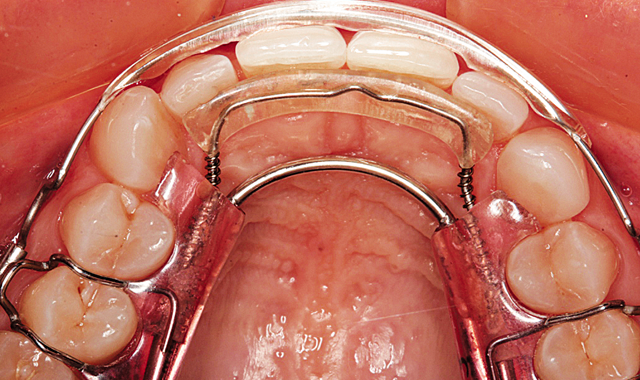

During the next twelve weeks, Mary wore the two Inman Aligners for at least sixteen hours a day. She presented to the office for additional IPR every two weeks. The Inman Aligner can be seen in place from the incisal view on the maxillary arch after twelve weeks in Figure 9.

Fig. 9